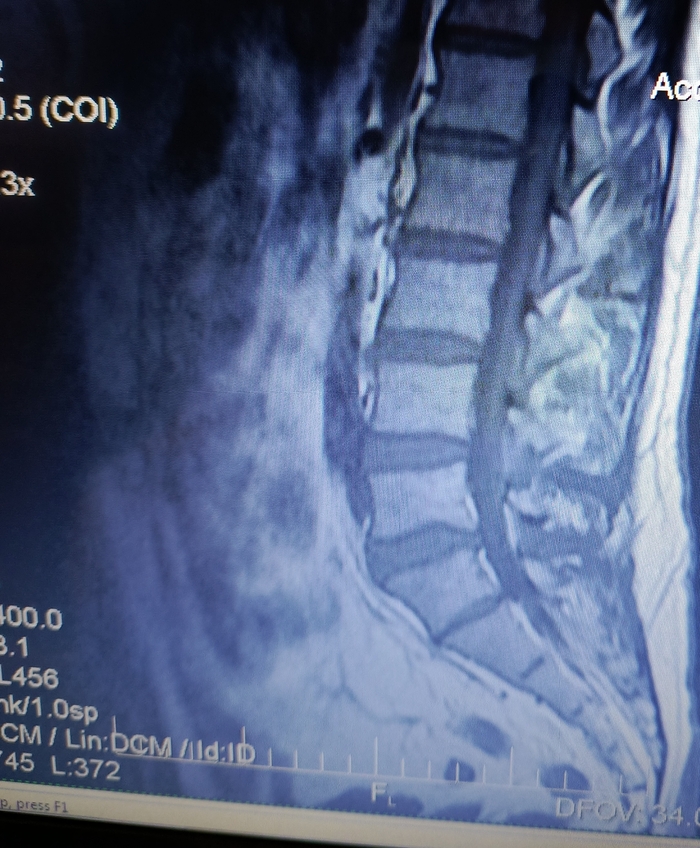

Есть боли в ПОП, в 2020 году на основании МРТ был поставлен диагноз: "Грыжа диска L5/S1. Протрузия диска L4/5."

В 2024 году во время очередного обострения делал повторно МРТ. Диагноз: "Грыжа диска L5/S1. Протрузия диска L4/5. При сравнении с данными 2020 года динамика отрицательная."

2025 год. После очередного обострения и стандартного лечения острая боль прошла, но остались тупые тянущие боли. На днях сделал повторно МРТ. Диагноз: умеренный остеохондроз, с поражением диска L5/S1 с диффузно медианной протрузией.

Собственно вопрос, к тем кто разбирается, действительно ли на данных снимках нет грыжи?

Снимки (с экрана) ниже. Откликнувшихся заранее благодарю.